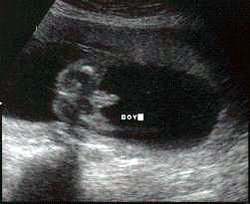

الولد

ولد في الأسبوع ال 15

ولد في الاسبوع ال16

الأسبوع ال17

الأسبوع ال18